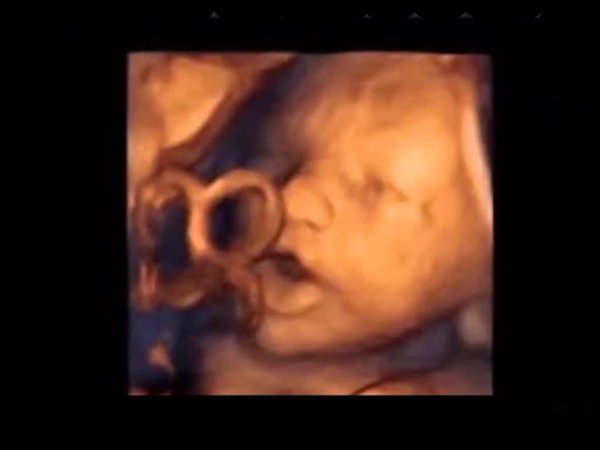

Έμβρυο «τραγουδά» μέσα στη μήτρα [βίντεο]

Τα έμβρυα μπορούν να ακούσουν αρκετά καλά από τη 16η κιόλας εβδομάδα της κύησης.

Για πρώτη φορά στα χρονικά, επιστήμονες από το Ινστιτούτο Marques της Βαρκελώνης κατάφεραν να αποδείξουν ότι ένα έμβρυο μπορεί να ανιχνεύσει τους ήχους και μάλιστα ότι αντιδρά σε αυτούς, κουνώντας το στόμα και τη γλώσσα του.

Αποτελεί κοινή παραδοχή ότι τα αφτιά ενός εμβρύου έχουν πια αναπτυχθεί πλήρως μέχρι τη 16η εβδομάδα της εγκυμοσύνης. Μέχρι τώρα όμως οι επιστήμονες πίστευαν ότι ένα έμβρυο μπορεί να ακούσει από τη 18η εβδομάδα της κύησης και έπειτα.

Η επικεφαλής της μελέτης Δρ Marisa Lopez-Teijon δηλώνει πως τα ευρήματα αποδεικνύουν ότι το έμβρυο ανταποκρίνεται στη μουσική που μεταδίδεται ενδοκολπικά «σαν να προσπαθεί να μιλήσει ή να τραγουδήσει»!